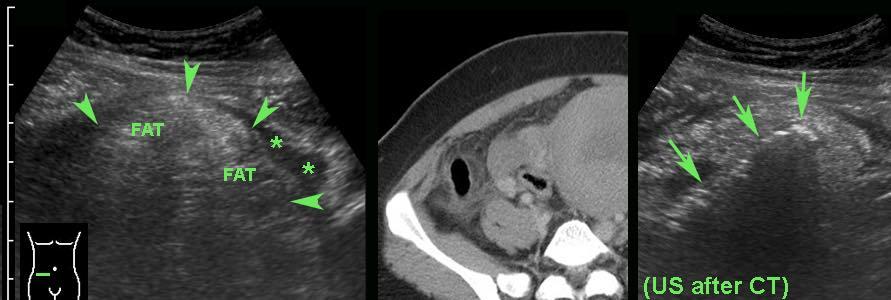

Ở người phụ nữ cao tuổi này với đau bụng không điển hình và suy thận, CT không tiêm thuốc cản quang cho thấy hình ảnh ruột thừa nghi ngờ viêm.

Siêu âm tập trung với đầu dò tần số cao xác nhận ruột thừa nằm ở phía trước bụng đang trong tình trạng viêm.

Ở bệnh nhân béo phì này, CT xác định một ruột thừa nằm sâu, có thể đang viêm (mũi tên) ở khoảng cách 11 cm tính từ da.

Siêu âm tập trung với kỹ thuật ép dần (graded compression) đã rút ngắn khoảng cách này xuống còn < 3 cm, cho phép sử dụng đầu dò tần số cao, qua đó cho thấy ruột thừa không thể ép xẹp và đang trong tình trạng viêm (mũi tên).

Ở người đàn ông trẻ này, ruột thừa không thể xác định được trên CT do thiếu mỡ trong ổ bụng.

Siêu âm dễ dàng xác định được ruột thừa bình thường.